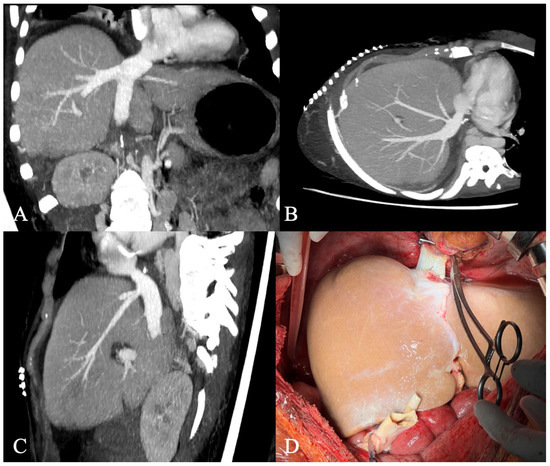

A 25-year-old woman with decompensated liver cirrhosis and complete inferior vena cava (IVC) occlusion was referred to our department for liver transplantation. The etiology of cirrhosis was Budd-Chiari syndrome (BCS) related to systemic lupus erythematosus, autoimmune hepatitis, and primary biliary cholangitis (AIH-PBC) overlap [...] Read more.

A 25-year-old woman with decompensated liver cirrhosis and complete inferior vena cava (IVC) occlusion was referred to our department for liver transplantation. The etiology of cirrhosis was Budd-Chiari syndrome (BCS) related to systemic lupus erythematosus, autoimmune hepatitis, and primary biliary cholangitis (AIH-PBC) overlap syndrome. Transplantation was feasible due to an extensive collateral circulation of pre-vertebral veins that drained blood from the lower extremities and both kidneys to the azygos-hemiazygos veins. This venous anomaly enabled the excision of the obstructed retrohepatic IVC, followed by an alternative anastomosis of the suprahepatic IVC to the right atrium without reconstruction of the infrahepatic IVC. Despite good venous patency and normalization of liver graft function, the patient developed cecum perforation, cardiovascular and respiratory insufficiency, which led to the patient’s death two months after transplantation. This case report supports an individual approach and highlights the feasibility of liver transplantation despite an extensive IVC thrombosis. To our knowledge, it is the first description of the application of a deceased donor liver transplantation in patients with AIH-PBC overlap syndrome and lupus-related BCS. A concise review of published literature on IVC-atrial anastomosis in adult liver transplant recipients is provided, and the technique is discussed based on our recent experience. Full article